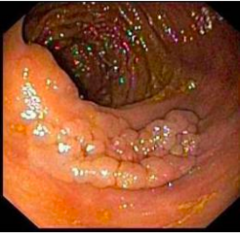

Papillary

Exophytic growth pattern with fibrovascular cores supporting proliferative epithelium Cauliflower or coral shaped structures with branching fibrovascular core

Bosselated

-Having bumps that stick out -Rounded Probuterances